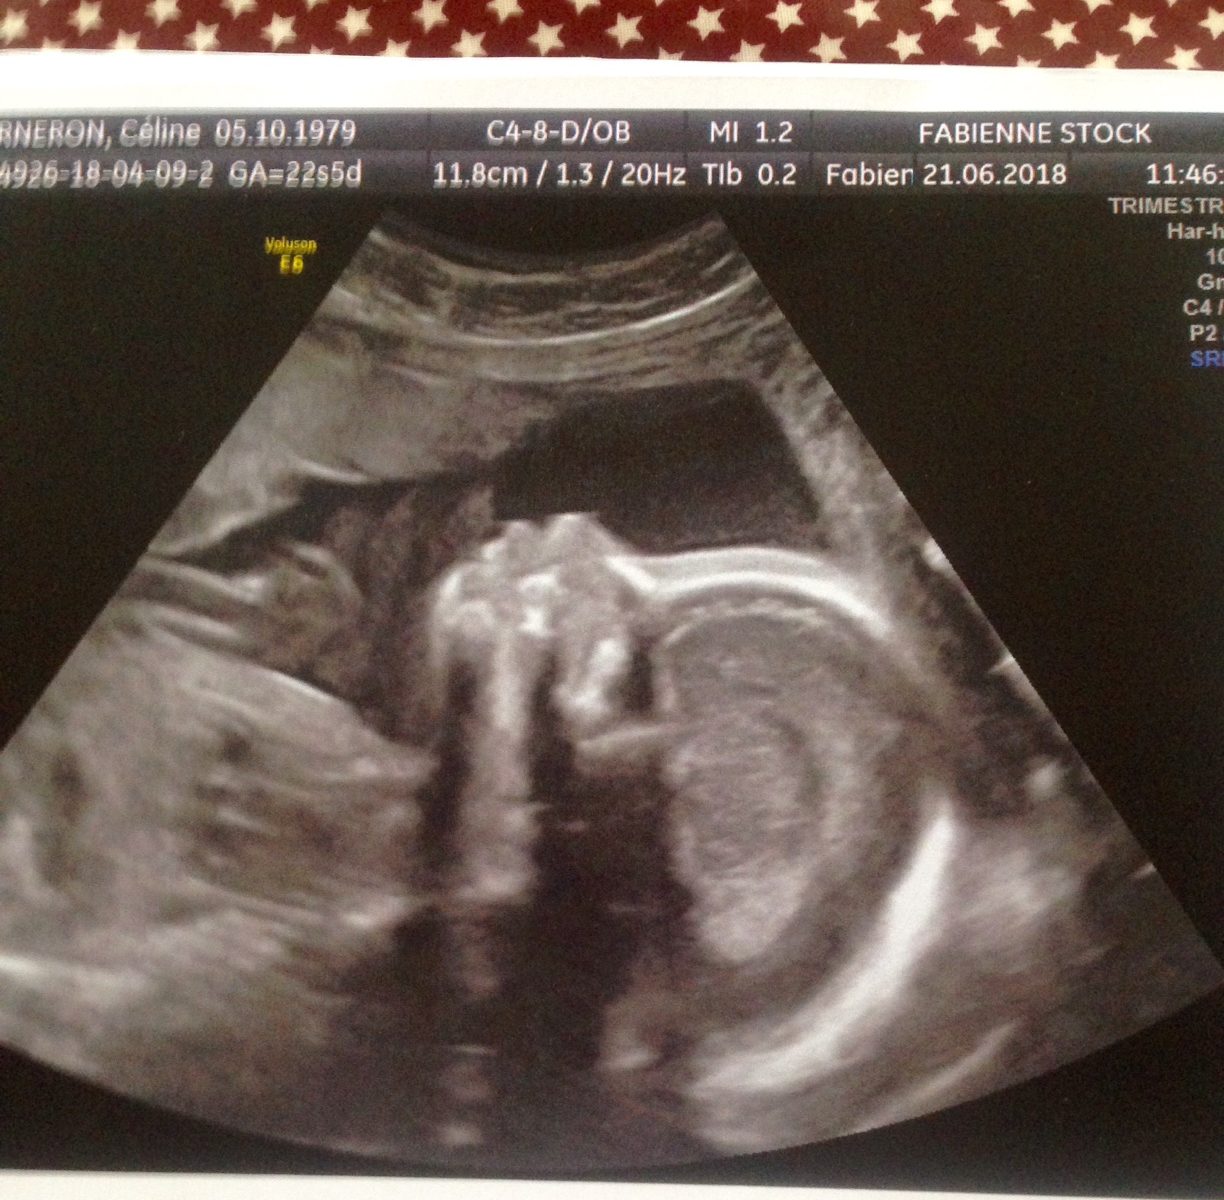

Après un début d ‘année sur les chapeaux de roues , premières en janvier de mon one woman show » Princesse Bernard » au théâtre du grand rond à Toulouse puis deux mois de résidences et une première pour la pièce « Quelqu un va venir » de Jhon Foss au festival « Spring Festival »( cf teaser plus bas ) je suis actuellement en gestation et oui je suis enceinte d une petite fille arrivée sur terre prévue fin octobre !

en attendant une petite photo d elle intra utérus 😉